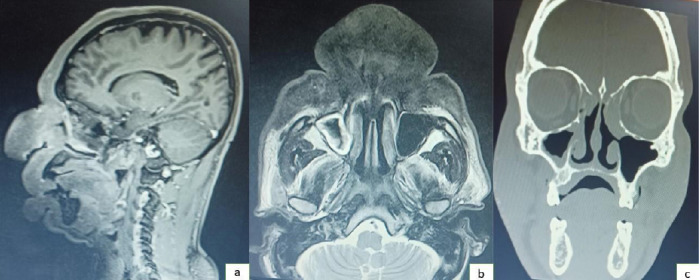

Rhinoentomophthoromycosis: An Enigma in Itself

{"title":"Rhinoentomophthoromycosis: An Enigma in Itself","authors":"Smrithy Sivadas K, Renita Lorina Castelino","doi":"10.4274/balkanmedj.galenos.2025.2024-12-7","DOIUrl":null,"url":null,"abstract":"","PeriodicalId":8690,"journal":{"name":"Balkan Medical Journal","volume":" ","pages":"369-370"},"PeriodicalIF":3.8000,"publicationDate":"2025-07-01","publicationTypes":"Journal Article","fieldsOfStudy":null,"isOpenAccess":false,"openAccessPdf":"https://www.ncbi.nlm.nih.gov/pmc/articles/PMC12240223/pdf/","citationCount":"0","resultStr":null,"platform":"Semanticscholar","paperid":null,"PeriodicalName":"Balkan Medical Journal","FirstCategoryId":"3","ListUrlMain":"https://doi.org/10.4274/balkanmedj.galenos.2025.2024-12-7","RegionNum":4,"RegionCategory":"医学","ArticlePicture":[],"TitleCN":null,"AbstractTextCN":null,"PMCID":null,"EPubDate":"2025/3/28 0:00:00","PubModel":"Epub","JCR":"Q2","JCRName":"MEDICINE, GENERAL & INTERNAL","Score":null,"Total":0}